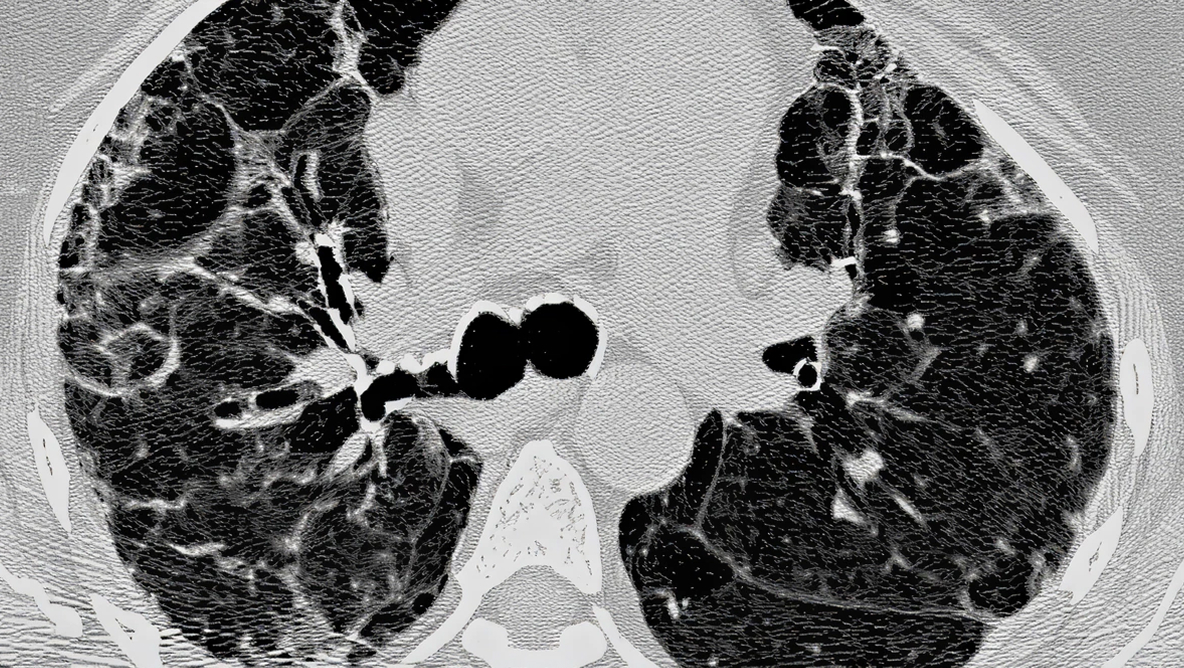

72‑letni mężczyzna z UIP. Badanie HRCT wykazuje rozsiane zmiany siateczkowe oraz trakcyjne rozstrzenia oskrzeli i rozstrzenia oskrzelików.

TRAKCYJNE ROZSTRZENIE OSKRZELI / ROZSTRZENIE OSKRZELIKÓW

Cechy

• Nieprawidłowe i nieregularne rozszerzenie oskrzeli/oskrzelików w wyniku zapalenia dróg oddechowych (czasami odwracalne) lub zwłóknienia płuc

• W badaniu HRCT widoczne jako zwiększenie średnicy dystalnych dróg oddechowych (brak obwodowego zmniejszania się średnicy, widoczność w podopłucnowych częściach płuca w odległości co najmniej 20 mm od opłucnej)

• Na obrazie widoczne są jako rurkowate lub torbielowate przestrzenie powietrzne, w zależności od orientacji oskrzeli na przekroju

• Różnicowanie pomiędzy trakcyjnymi rozstrzeniami oskrzeli a zmianami typu „plastra miodu” jest czasem trudne na przekrojach osiowych. Przydatne są przekroje strzałkowe lub czołowe